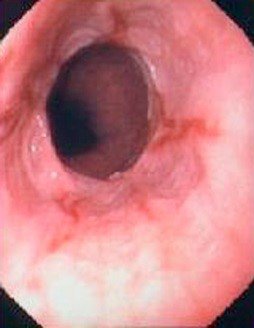

QB-nun epifrenik divertikulu

Pulsion, yalançı divertikuldur. QB-nun distal 10 sm hissəsində, aşağı sfinkterin üstündə yerləşir. Kiçik divertikullar adətən əlamətsiz olur, böyük divertikullar isə disfagiya, divertikulit və fistul törədə bilirlər.

Diaqnostika

Dəqiqləşdirmə

Diaqnozun dəqiqləşdirilməsi üçün kontrastlı şüa diaqnostikası üsulları (Rh-qrafiya və ya KT) və endoskopiya aparılmalıdır.

- Endoskopiya - divertikulun perforasiyası təhlükəsinə görə çox ehtiyatla aparılmalıdır. QB-nun xəstəliklərinin və paraezofageal yırtıqların diferensiasiyası üçün mühümdür.